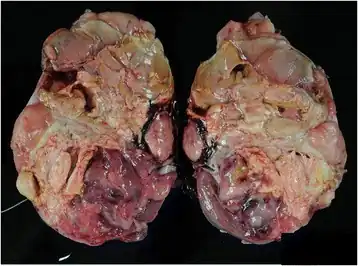

| Gross pathological findings. The tumor weighed approximately 750 g and measured 15 × 12 × 9 cm. The left kidney is replaced by the neoplasm. Calcification is apparent around the necrotic tissue | |

Typical gross features include large size (mean diameter 11.3 cm), a mucoid texture, foci of necrosis, and prominent cyst formation.[3]